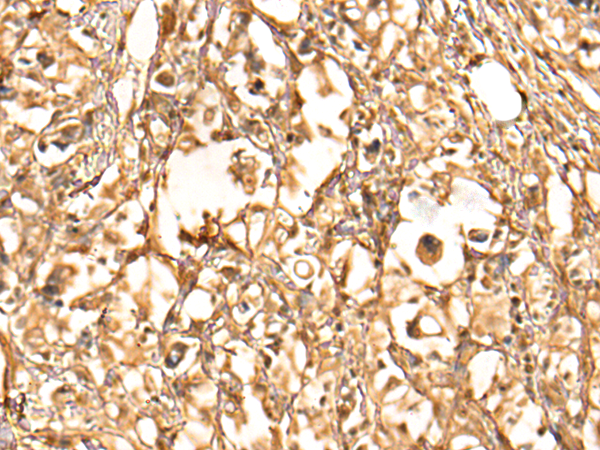

The image is immunohistochemistry of paraffin-embedded Human liver cancer tissue using (BTF3L4 Antibody) at dilution 1/30. (Original magnification: ×200)

The image is immunohistochemistry of paraffin-embedded Human gastric cancer tissue using (BTF3L4 Antibody) at dilution 1/30. (Original magnification: ×200)